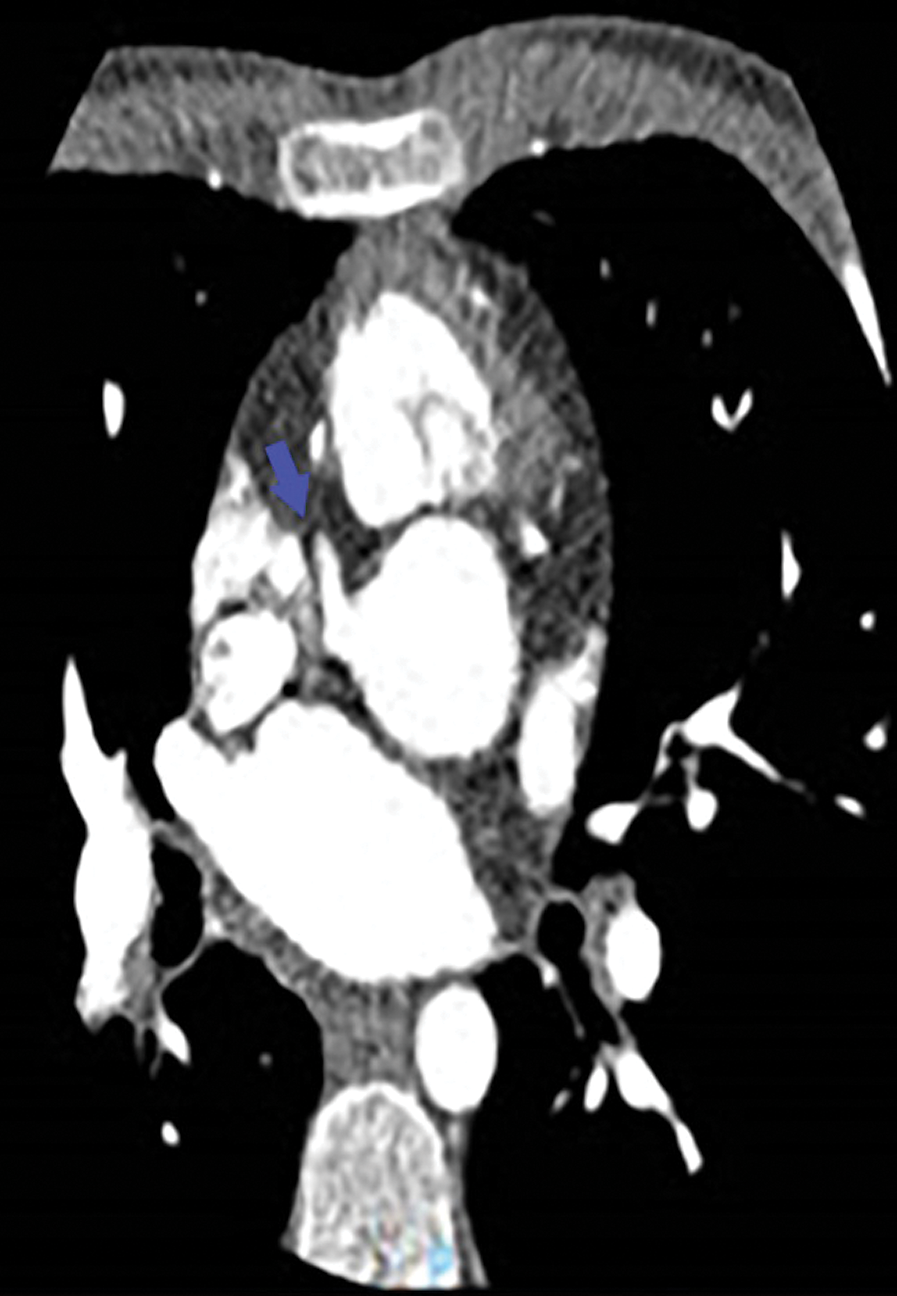

The patient was asymptomatic. The physical examination at admission showed a systolic murmur 3/6 maximum at the pulmonary focus and radiating into the back and no signs of heart failure was present. The electrocardiogram was normal, and the echocardiographic study showed a mild septal dyskinesia. The cardiac catheterization and the angio-CT demonstrated a rare coronary pattern: 1- proximal LAD and 2-RCA-Cx-distal LAD pattern (posterior loop) and severe proximal stenosis of “LAD” arising from pulmonary artery (Figs. 1–4).

Figure 3: Angio-CT: Only the right coronary artery arises from the aorta